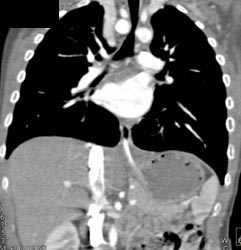

Airway Narrowing Due to Double Arch